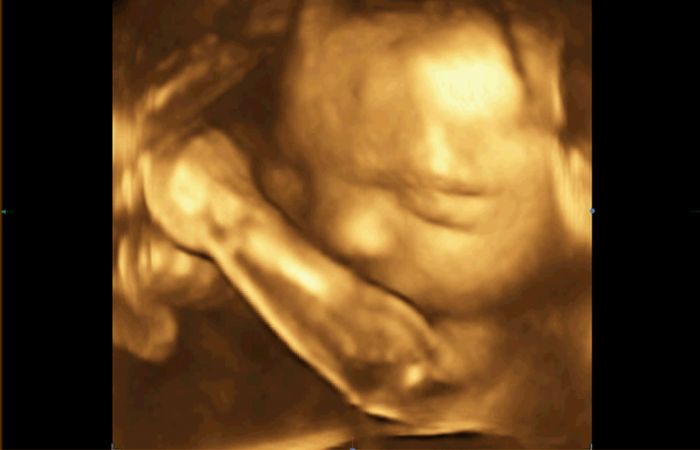

No a minulou středu 3D/4D u mého obvodního gynekologa ( má opravdu dobře vybavenou ordinaci). Nejdřív jsem si myslela, že se nám to moc nepovedlo, páč se nám většinu času schovával za ručičku, ale dle toho, co slyším od ostatních to vlastně byl úspěch

Přikládám fotečky uložené z videa na DVD , které nám dal dr.